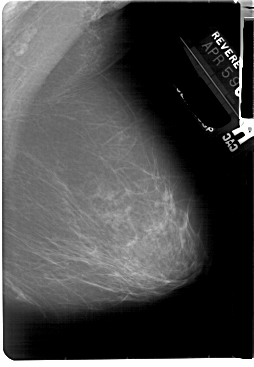

A_1855_1.RIGHT_CC

RIGHT_CC LINES 5491 PIXELS_PER_LINE 3541 BITS_PER_PIXEL 12 RESOLUTION 43.5 NON_OVERLAY